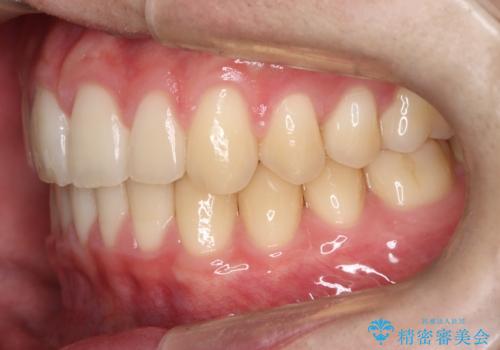

【ワイヤー矯正】すきっ歯を治したい

- 主訴:上の前歯のすきっ歯を治したい。

今回のような空隙歯列に対したは、マウスピース矯正・ワイヤー矯正どちらの方法でも矯正治療可能と説明し、ワイヤー矯正を希望されました。

上顎中切歯間の隙間の他にもフロスが抵抗なく入るスペースが上顎は数か所ありました。スペースを閉じ下顎の歯列弓との調和をとるためIPRを行いました。

下顎の舌側傾斜気味の前歯も唇側へ歯軸傾斜させています。

矯正期間:1年2か月